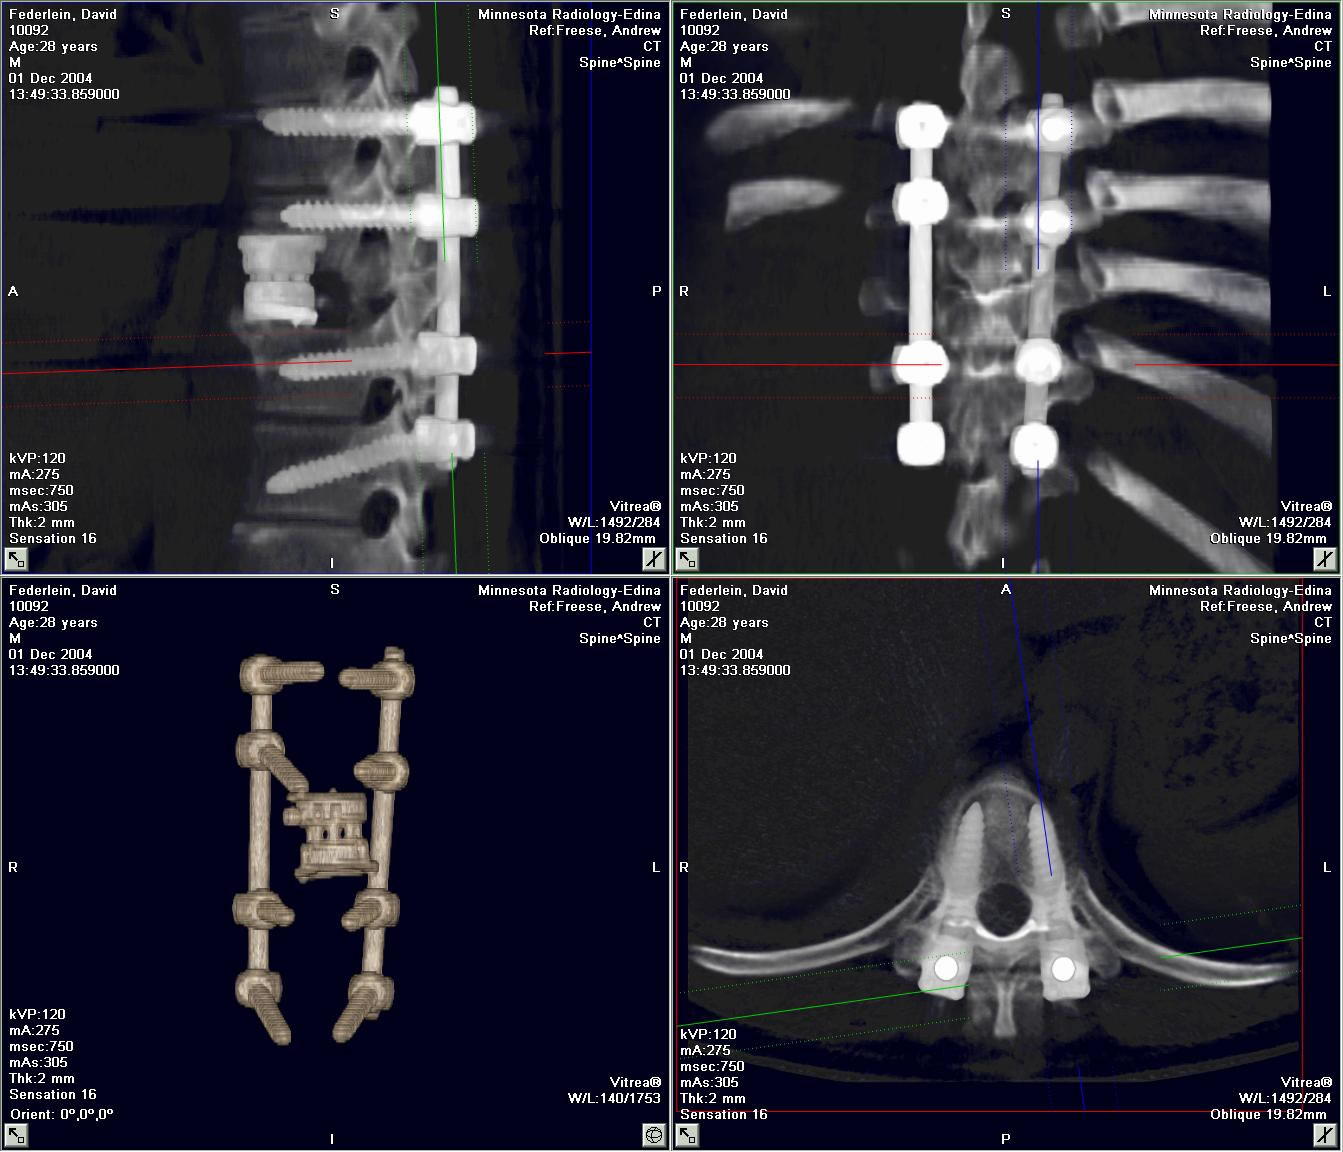

I was diagnosed with Solitary Plasmacytoma of Bone in early 2004.  By the time it was caught in MRI scans, my 9th thoracic vertebrate was completely obliterated.  I could barely walk and was losing feeling from the waist down.  In November 2004, I had an 11-hour operation to restore my spine using bone grafts and titanium implants, and began radiation treatments shortly thereafter.  I have 95% of my mobility back, 100% feeling in my legs again, and I now do bone surveys, blood tests and bone marrow biopsies every 3 months or so to determine if my Solitary Plasmacytoma has developed into Multiple Myeloma.  Like Randi, I owe my life to very talented, and dedicated medical professionals.  I owe my life to science.

Firstly, I want to address the clique of “alternative therapists” that advocate magnet therapy.  The average power of a kitchen magnet’s magnetic field, if of high quality, is roughly 1000 gauss (.1 tesla.)  These magnets sold as bracelets, rings, or pendants are said to cure chronic pain of muscles and bones.  The average MRI (Magnetic Resonance Imaging) scan has a magnetic field power of 30,000 gauss (3 tesla.)  Here is the MRI scan of my spine before the surgery:

I can assure you, I was still in pain after that MRI.  If I wasn’t cured of pain after that, surely it follows that a kitchen magnet is not actually relieving pain.  The power of suggestion to temporarily relieve symptoms is known as the Placebo Effect.  In the long run, placebo does nothing.